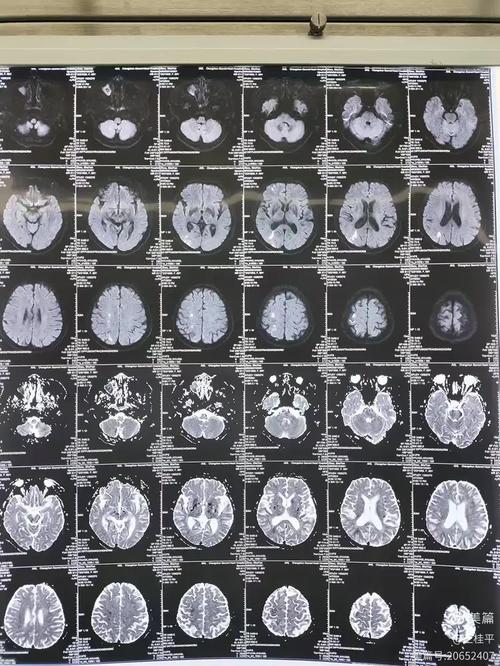

(图片来源网络,侵删)

- 头颅MRI+DWI+MRA/CTA: MRI是发现脑梗病灶最敏感的检查,MRA(磁共振血管成像)或CTA(CT血管成像)可以查看脑血管有无狭窄或闭塞。